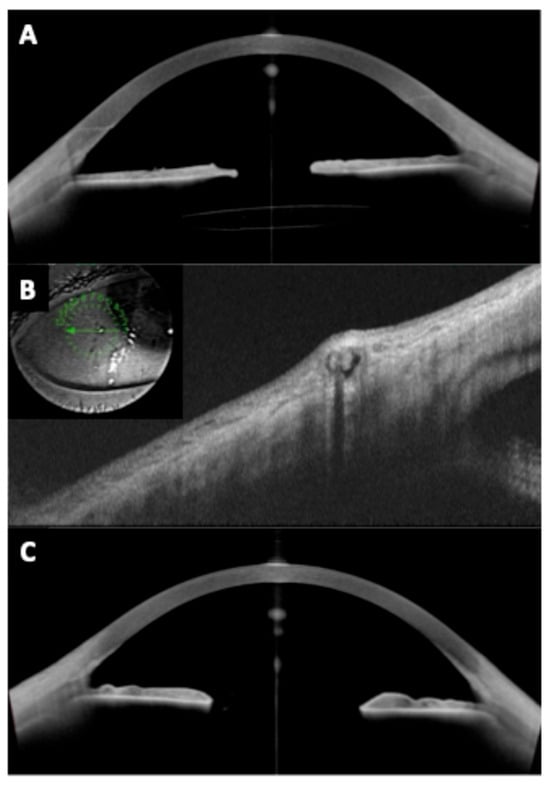

One of the foremost uses of anterior segment OCT is to measure the central vault of posterior chamber pIOLs like the ICL (Figure 1). The vault is defined as the perpendicular distance between the posterior pIOL surface and the anterior crystalline lens capsule. A widely cited target considered ideal is a vault of approximately 250–750 μm in normal lighting conditions. In a properly sized ICL, the vault remains sufficient even under physiological changes [17,18,26,27]. Normative vault ranges have been established in large studies using OCT and reporting an average vault of around 500–600 μm with standard deviations of ~200 μm [28,29,30,31].

Postoperative vault is critical to minimize complications. Approximately 5–10% of eyes may end up with low (<250 μm) or high (>1000 μm) vaults even with formula-based sizing [14]. OCT can detect scenarios like an oversized ICL causing iris convexity (iris pushed forward by a high vault) or an undersized ICL that is “collapsing” onto the crystalline lens. It is indispensable to identify these outliers early so that prophylactic measures can be taken (e.g., prophylactic iridotomy for a high vault to prevent block, or ICL exchange for a very low vault to prevent cataract) [17].

Figure 1. Vault assessment and angle configuration in phakic IOLs. (A,B) Preoperative anterior segment optical coherence tomography (AS-OCT) and optimal vault (~500 µm) after implantable Collamer lens (ICL) implantation, respectively; (C,D) Preoperative AS-OCT and high vault (>1000 µm) after ICL implantation, respectively; (E,F) Preoperative AS-OCT and low vault after ICL implantation (<250 µm), respectively.